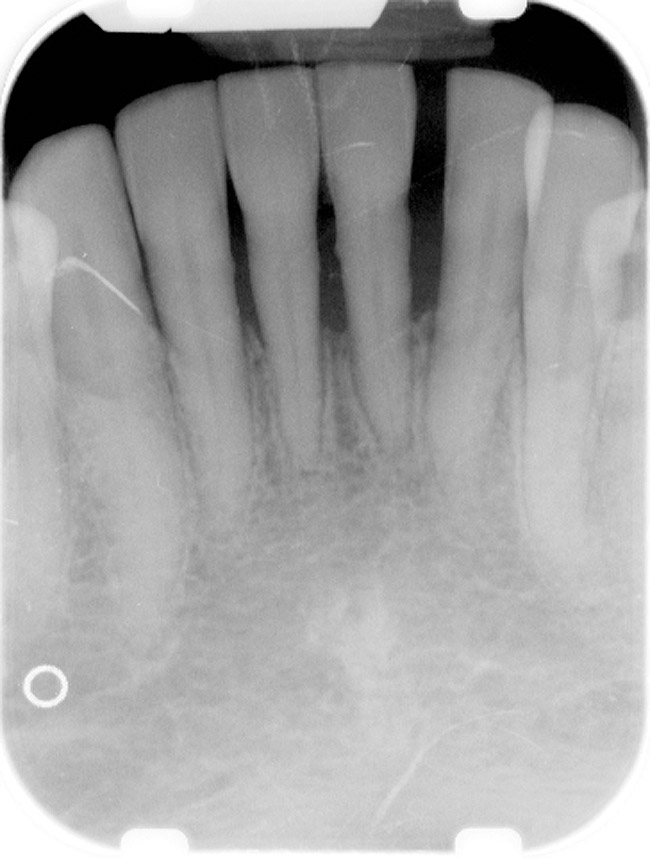

Figure 4  Radiograph of oral bisphosphonate user.

Figure 4

Under the sextant approach, one quadrant is treated and the patient is left to heal for 2 months before proceeding to any additional quadrants. While the patient heals, a 10-day course of antibiotics and 2 months of twice-daily chlorhexidine rinsing may be prescribed. Figure 4 shows a patient who was taking oral bisphosphonates for 3 years and was treated with the sextant approach. As seen in the radiograph, the patient has one molar in the lower right quadrant. This tooth was extracted and the patient was given 2 months to heal (Figure 5 and Figure 6). The patient was placed on antibiotics and chlorhexidine rinse. After 2 months, no signs of BRONJ were observed, and the anterior teeth were scheduled for extraction. They were extracted as atraumatically as possible, and the site was sutured (Figure 7 and Figure 8). The patient then was given another 2 months to heal, following the previous protocol. After 2 months of healing, no BRONJ was observed (Figure 9). The patient was able to move forward with the prosthesis.